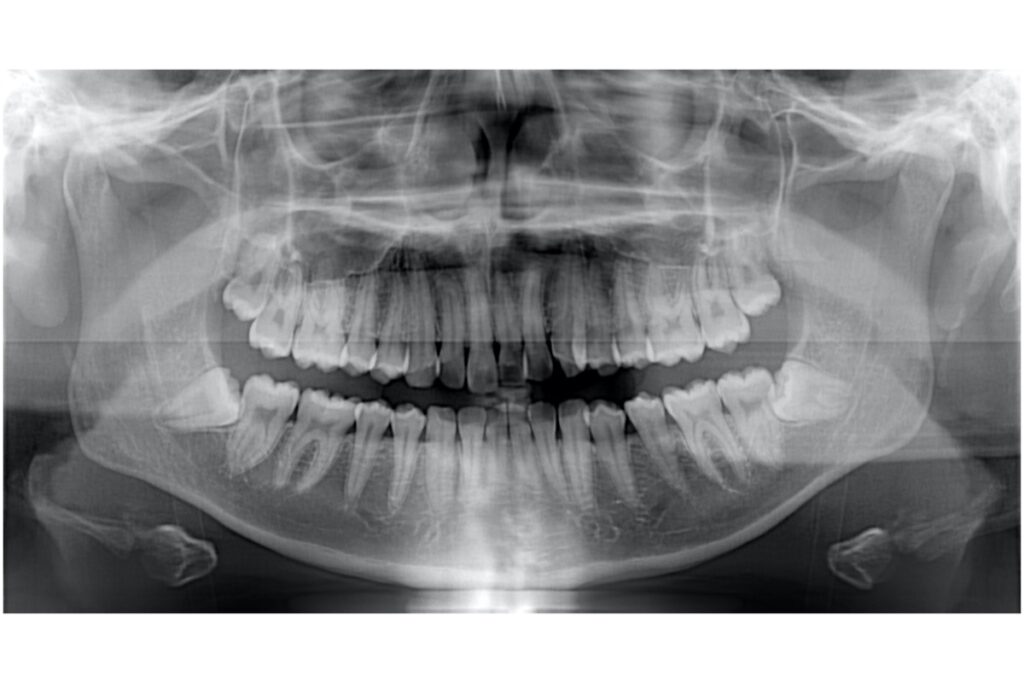

矯正治療において「抜歯するか、しないか」は、患者さんの希望だけでは判断できません。レントゲン、歯型、口腔内写真などをもとにした詳細な分析と診断が不可欠です。